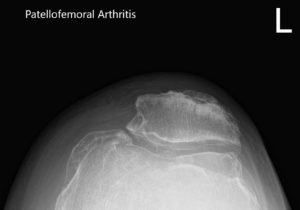

Considering his lifestyle limiting knee pain, various management options including both surgical and nonsurgical were discussed with him at length. He was considered a candidate for custom left knee total replacement. Risks, benefits and potential complications were discussed with him in detail. He agreed to the plan. Imaging studies revealed severe tricompartmental osteoarthritis of the left knee joint.

Preoperative X-ray of the left knee showing AP and lateral view of the knee with a skyline view of the patella.